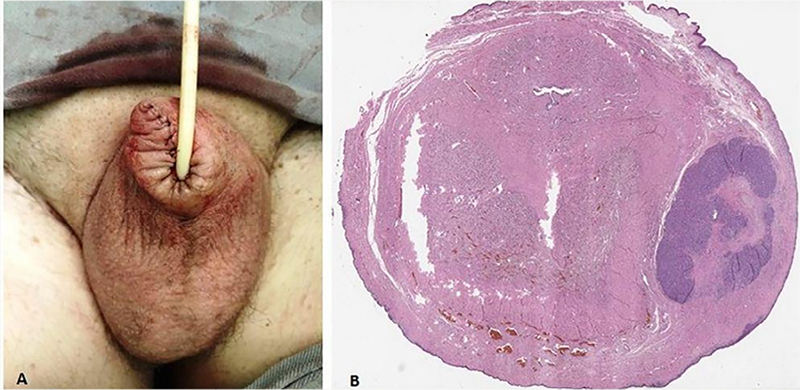

The anatomopathological showed a 7mm thick Clark IV nodular melanoma, with ulceration, without angiolymphatic and perineural invasion. Clinical staging of the disease was performed with chest X-ray, abdominal and pelvis tomography (CT) and cranial magnetic resonance imaging (MRI), with no evidence of regional lymph node enlargement or systemic metastases. Due to the locally advanced clinical stage (T4bN0M0 – ulcerated lesion above 4mm), PET/CT was performed, whose uptake also did not show lymph node or systemic disease. The authors performed partial penectomy and investigation of sentinel lymph node with local technetium injection 12 hours before the procedure (Figure 3), in addition to bilateral inguinal lymphadenectomy at the same surgical time, due to the absence of clinical evidence in the literature that proves the total effectiveness of the sentinel lymph node in the identification of lymph node micrometastasis of penile melanoma, since the lymphatic drainage of the penis is crossed, as it is a midline organ. The margin was subsequently enlarged by 2cm due to impairment (Figure 4).

Figure 4 A. Post-operative result of penectomy and margin expansion; B. The anatomopathological study indicated vertical growth of the tumor, although there was an extensive lentiginous component “in situ”, associated with an area of ulcerated invasion with a thickness of 3.2mm that formed large groups of neoplastic melanocytes with atypical mitoses in the dermis and cavernous body.

There are microscopic satellite lesions that represent non-nodal regional tumor spread – pT3b pN1c pM0. The sentinel lymph node and the lymphadenectomy products showed reactive lymphoid hyperplasia, however the surgical margin was coincident with the lentiginous in situ component of the neoplasia. The surgical margin was then enlarged by 2cm, whose pathological and immunohistochemistry showed absence of neoplasia.